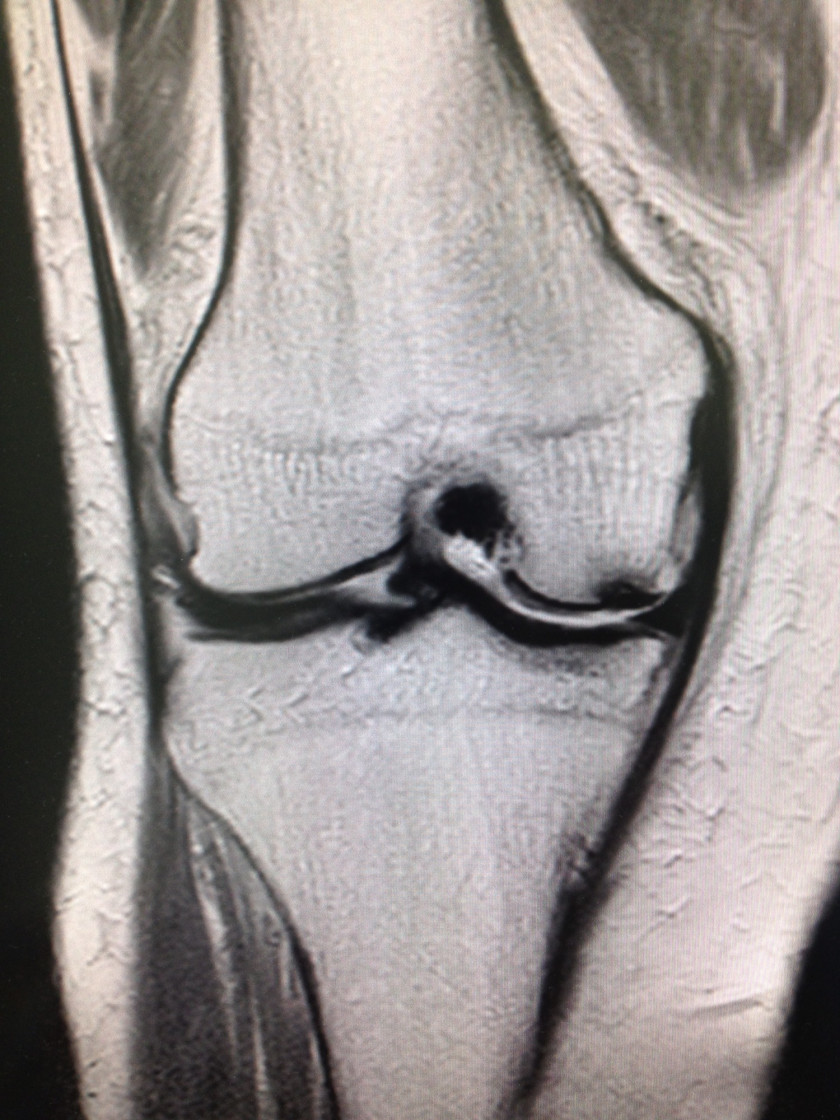

2017/02/21 MRIの威力

1月の初めに、チョットした段差で右ヒザ痛 出現。痛くて、近医 受診。

変形性膝関節症の診断にて、関節内注射 開始。それから・・・1月も終わり、2月も中旬になっても痛みは改善せず。友人から紹介され当院受診。発症後、1月半・・・。

ヒザは依然として、腫脹ありのまま。ピーンと察して、MRIオーダー。

本日、結果が出て以下の通り。大腿骨内顆部の関節面の黒い部分に気がつきましたか❓

MRIの他の画像も見ながら診断するのですが、単純レントゲン撮影では全く❓な異常がハッキリ。

さすが、形態学でイケる骨・関節領域で、絶大な威力を発揮するMRI。脳とはMRIの意味が違いますネ。変形性膝関節症ではなかった。と言うオハナシでした。